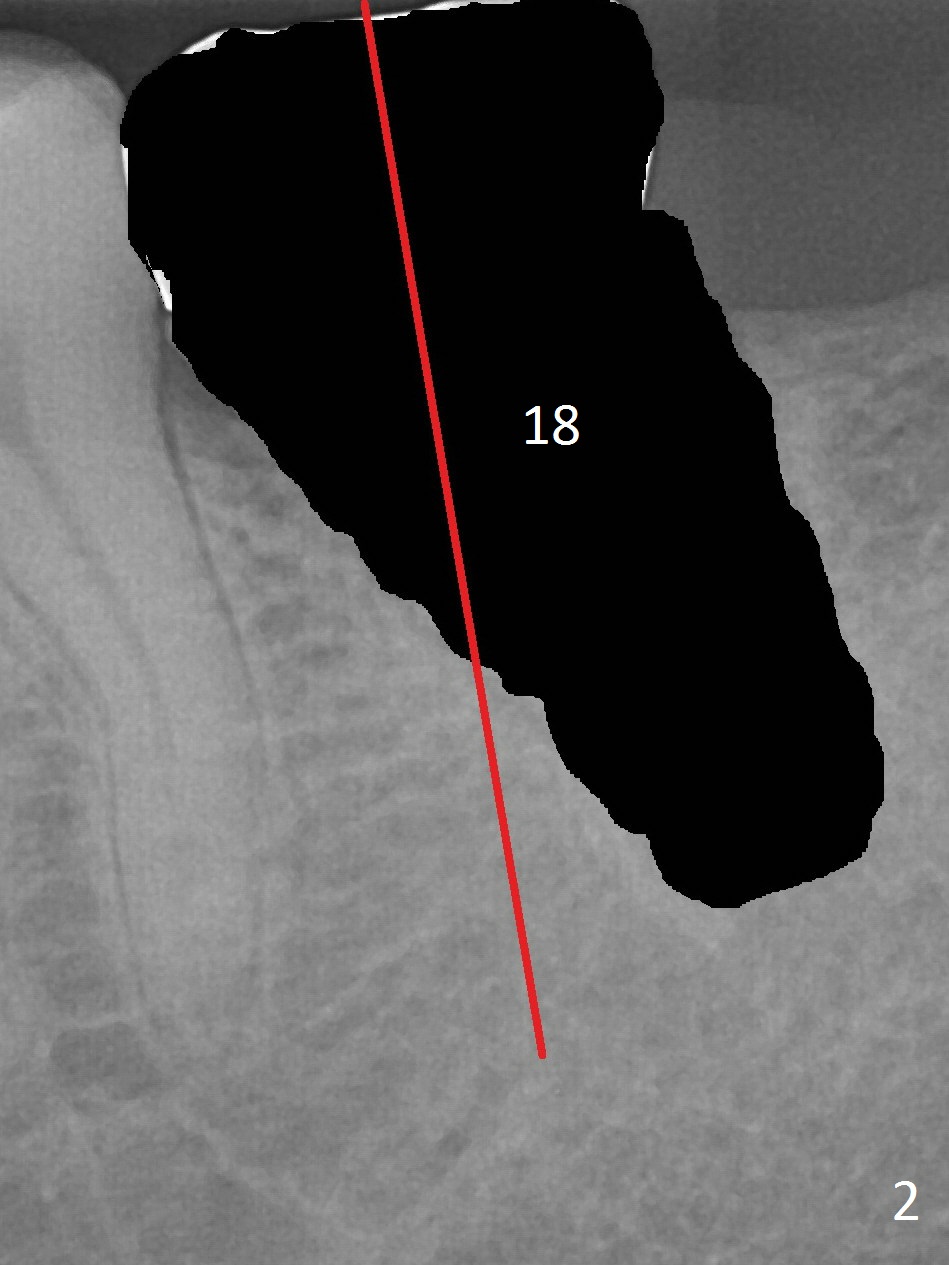

After extraction, the mesial slope of the socket seems to be an ideal osteotomy site (Fig.2 red line) with depth of 15 mm, as suggested by CBCT coronal section (Fig.3).  B: buccal.